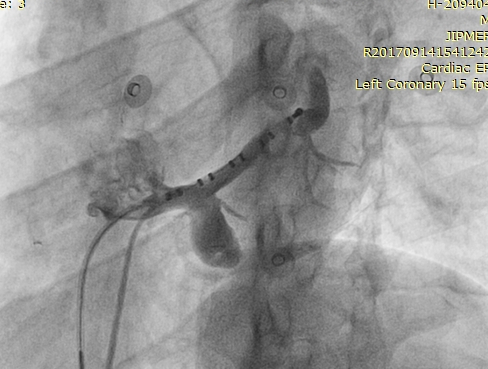

CS Diverticulum

Preexcited AF - note leads II and V6

ecg_af.jpg

Venogram

diverticulum.jpg